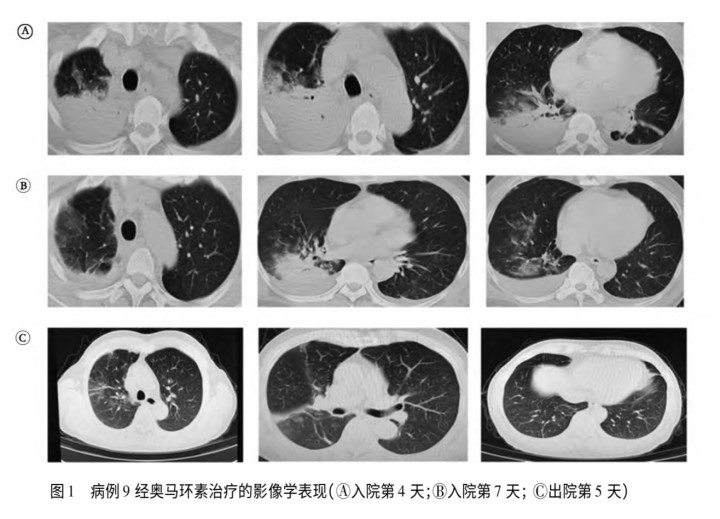

本年3月,中国科学院微生物参议所与航空总病院发布论文,先容了北京两例因感染鹦鹉热发生肺炎的女性病例,两东谈主在出现症状前均购买了宠物鹦鹉,这些鹦鹉到家后不久便出现了精神凄怨、羽毛蓬松、呼吸贫乏等症状,并最终牺牲;本年2月,安徽一男人购入4只鹦鹉当宠物,随后3只窘态牺牲,家东谈主也继续出现发热等症状。

北京航空总病院曾收治两名鹦鹉热患者,图为其斗争发病史及影像学查验。图/关系论文